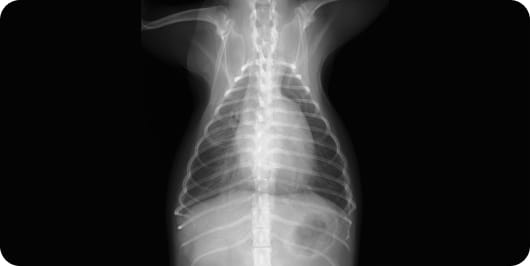

胸部レントゲン:心臓が拡大し、肺水腫(肺には水がたまっている)状態